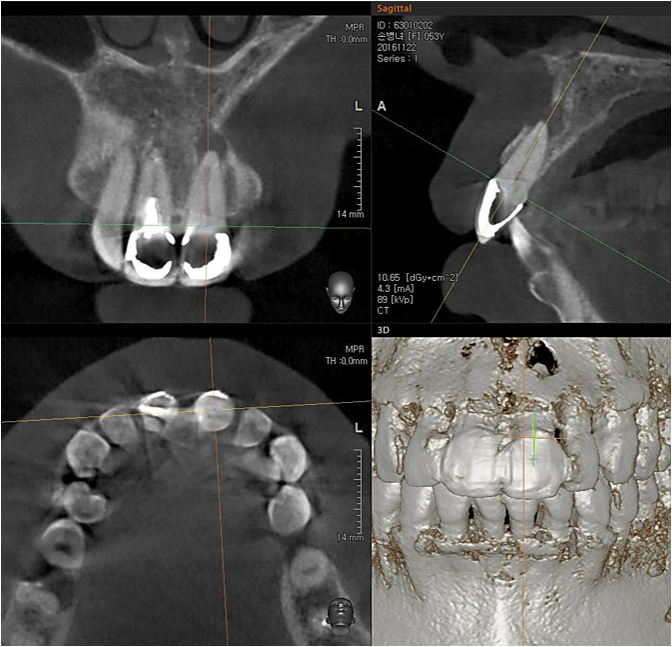

▲CBCT. Left central incisor had a apical lesion.